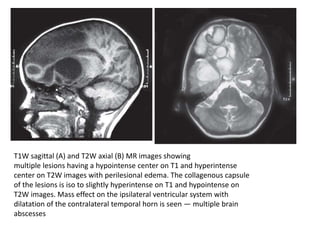

T1W sagittal (A) and T2W axial (B) MR images showing

multiple lesions having a hypointense center on T1 and hyperintense

center on T2W images with perilesional edema. The collagenous capsule

of the lesions is iso to slightly hyperintense on T1 and hypointense on

T2W images. Mass effect on the ipsilateral ventricular system with

dilatation of the contralateral temporal horn is seen — multiple brain

abscesses